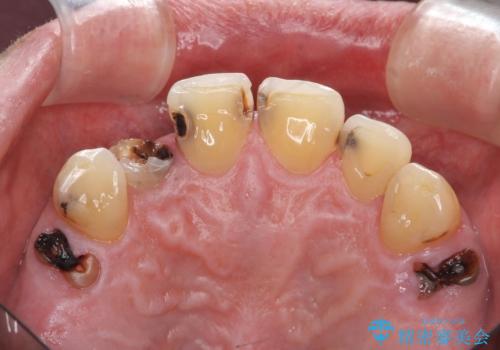

- 前歯の虫歯に気付きながらも放置し、一念発起し治療を希望され来院されました。

虫歯のマイクロスコープによる丁寧な除去、根管治療、深い虫歯に対する挺出(エクストリュージョン)および歯周外科を行ったのち精度の高いセラミッククラウン製作治療を計画します。

虫歯の放置により、根管治療や深い虫歯に対する処置が必要になりましたが丁寧に一つづつ処置を行ったことで抜歯をすることなく歯を残すことができました。